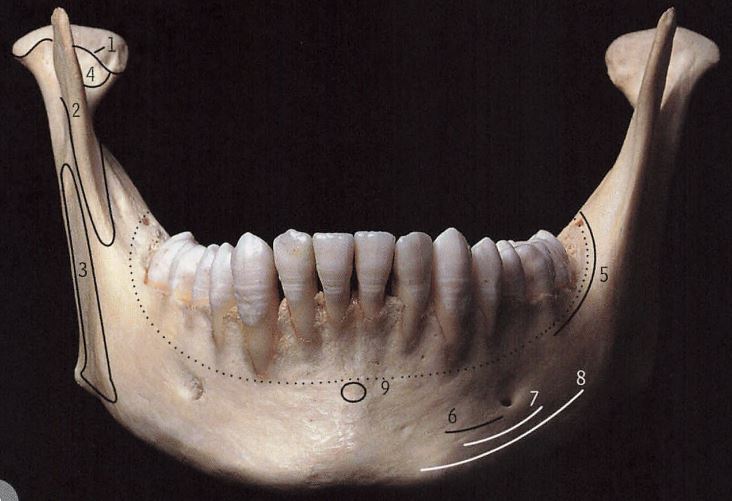

- 下颌骨是什么样的

下颌骨包括下颌体和双侧下颌支。所以我们看下颌骨有这么几个维度:横向、垂直向、前后向。

2、下颌角角度/垂直向

下颌角角度就是下颌体和下颌升支所成的角度。这个角度代表了侧面看一个人的轮廓,是有一个轮廓清晰的下颌角,还是一个柔和不显眼的下颌角。我们把下颌角度平的称为低角,把下颌角度陡的称为高角,把下颌角度正常的称为均角。

但是这两个维度是有联系的。一般来说,下颌角角度小的,脸短,脸方。下颌角角度大的,脸长。下颌角的角度是由基因决定的,其次还受咬肌力量大小的影响。如果咬肌力量大,就倾向于肌肉把下颌骨使劲往上拉,让下颌角角度变小,同时脸变短。如果肌肉力量不足,下颌角角度就会偏大,同时脸变长。

3、下颌的突缩、颏部的突缩/前后向

以上说的是下颌的突缩,还有颏部的突缩。颏部特指下颌联合最前部最突出的区域,这个区域是人类特有的,而其他灵长类是没有的,想想猩猩猴子的动物,他们都没有颏部。有了颏部就会有颏部上方的凹陷,叫做颏唇沟。颏部越突,颏唇沟越凹陷,越显得有下巴。